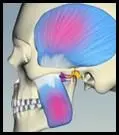

TMJ patients often have chronic pain and are in distress. Most of the pain comes from muscles both large and small that stabilize and move the jaw. This does not feel like muscle pain, but seems fixed and constant.

TM Joints + Teeth + Muscles Evaluation of all three components is required when signs and symptoms are present to determine a sound medical diagnosis.

Muscle analysis identifies which muscles generate pain. Charting muscle pain helps identify problems and conflicts between hard tissues. Some muscles may overdevelop and some may weaken or cramp.